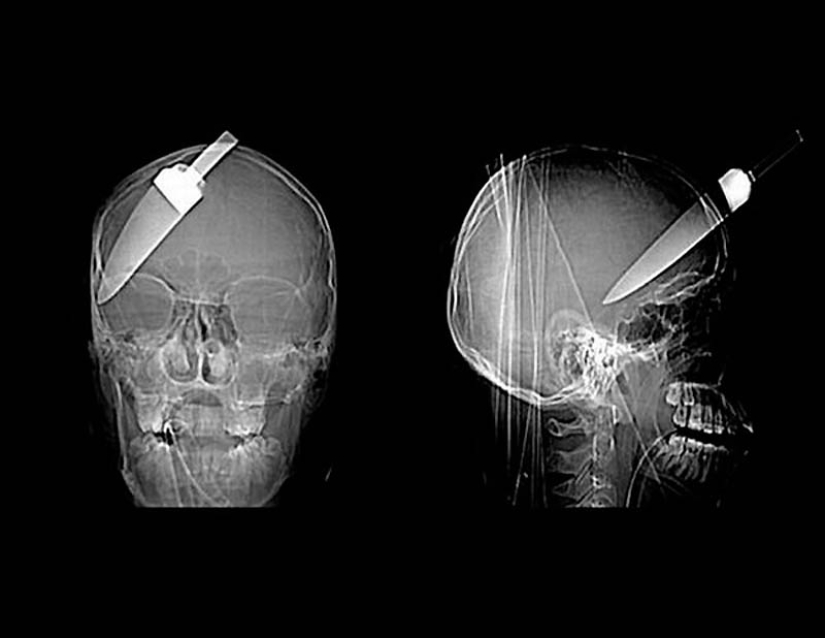

11. A spear from a harpoon that hit a 16-year-old boy in the head on a fishing trip.

16. A grenade in the prisoner's skull.